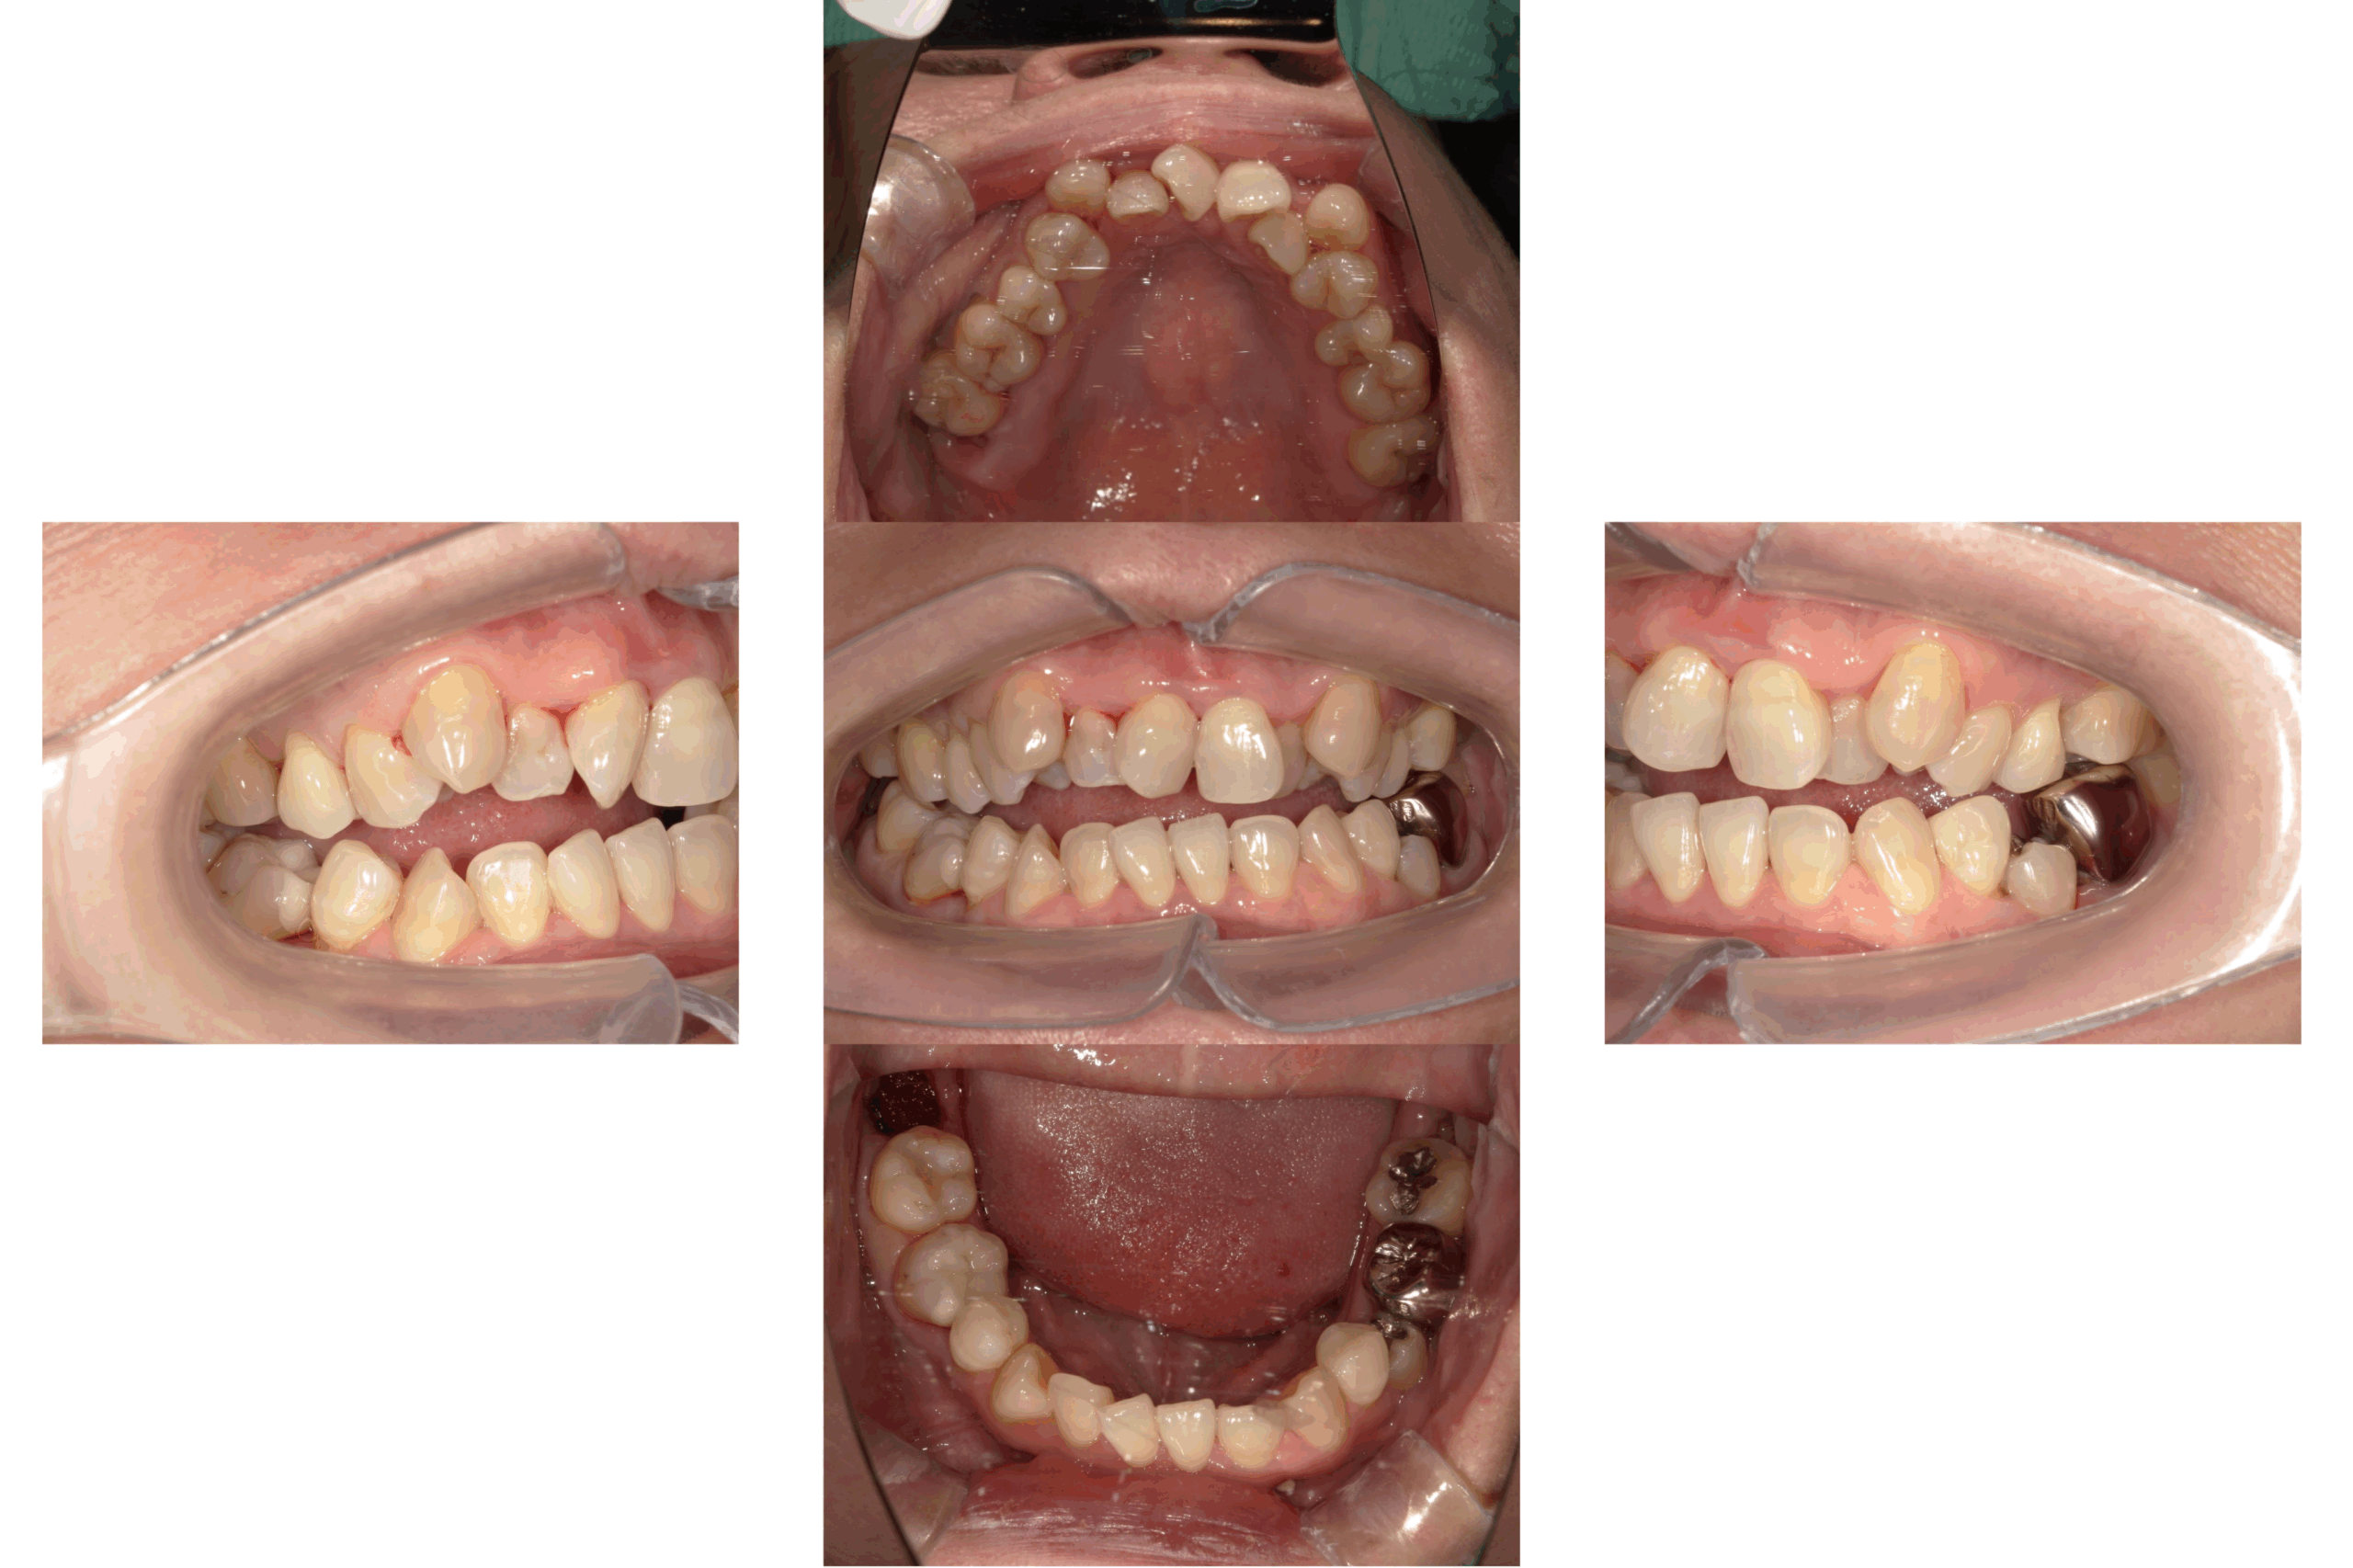

オープンバイト(開咬)のマウスピース矯正治療

Before

After

年齢

52歳

主訴

前歯でものが噛みきる事が出来ない。

治療期間

約2年

治療費

マウスピース型矯正装置 税込990,000円

治療内容

前歯でものを噛みきることが出来ず、年を取るにつれ奥歯が悪くなってきた気がするとのことでした。

ご相談させていただき、歯を抜かずにマウスピース矯正にて矯正治療を行わせていただきました。

治療期間は2年かかりましたが、見た目だけでなく前歯でしっかりものを噛めるようになり大変満足して頂けました。